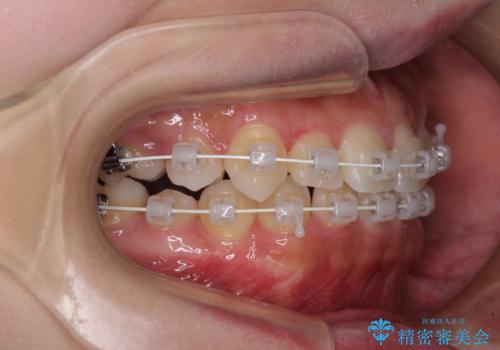

- 矯正装置

- 審美装置

- 治療期間

- 2年7ヶ月

前から5番目の乳歯は、後続永久歯である小臼歯と比べて幅径が大きいため、移動に時間がかかりましたが、きれいに仕上げることができました。